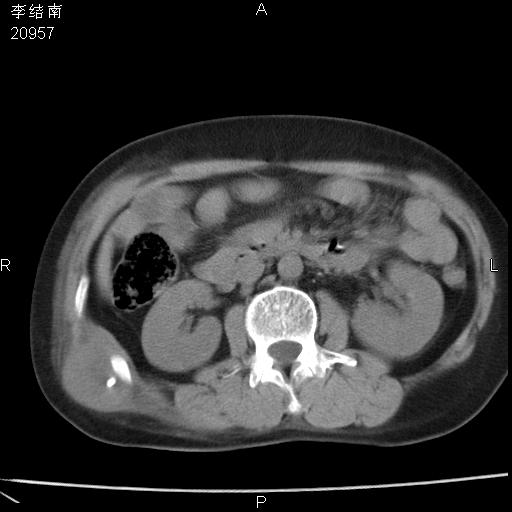

患者女,45岁,以右侧腰部包块来就诊,局部有压痛,皮肤颜色正常。因为是熟人扫的范围较大,患者有胆结石,胆源性胰腺炎病史。请大家看看,有手术病理。

肝包膜及腹壁病变考虑转移,食管改变需要明确良恶性。

可能大家觉得片子的质量不好,当时是做下腹部扫描,所以没有常规喝水,右腹壁的病灶当时是,密度不均有钙化影,局部骨质没见破坏,肝脏应该是受压的表现,所以当时考虑为腹壁的良性占位,各位老师考虑的神经源性肿瘤,我当时还真没想到,胰腺是胰腺炎治疗后改变.膈脚旁的混杂密度包快不好考虑什么,到上级医院做增强(腹部)+肺部平扫后,发现腹壁的病灶呈不均匀性强化局部可见囊性灶,当时考虑为腹壁结核,最具戏剧性的是膈脚旁的混杂密度灶确是胃的一部分,而腹壁的病灶确是脂肪瘤(简直不可思议)但是我亲眼所见在我们县医院开的.

很不好意思 ,患者后来手术切口裂开,临床医生作了病理证实是腹壁结核。

[病理诊断] CT13183腹壁结核!